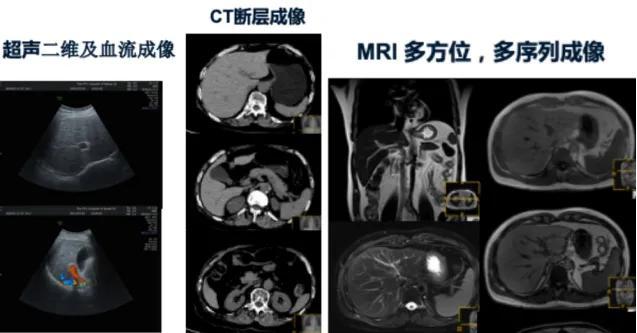

而在超声上没发现肿瘤时,或者超声上难以判断及难以确定肿瘤数目时,需要进一步的 “利器”去解决我们的问题。这个“利器”就是我们着重介绍的上腹部磁共振(MRI),是目前诊断肝癌最可靠的影像检查技术之一。

通过平扫和(或)增强磁共振扫描腹部,影像诊断医生根据扫描图像,对肝脏、胆囊、胆管、胰腺、脾脏、肾脏,及胃部、肠腔等病变,进行定位、定性分析,从而得出病变大致的诊断结果。

相对于超声和CT而言,上腹部MR具有无创,无辐射,多方位多参数,多序列成像的优点,组织分辨率高,比超声和CT提供更多信息;可以大幅度提高肝、胆、胰腺等重要脏器早期肿瘤及非肿瘤性病变的检出率。